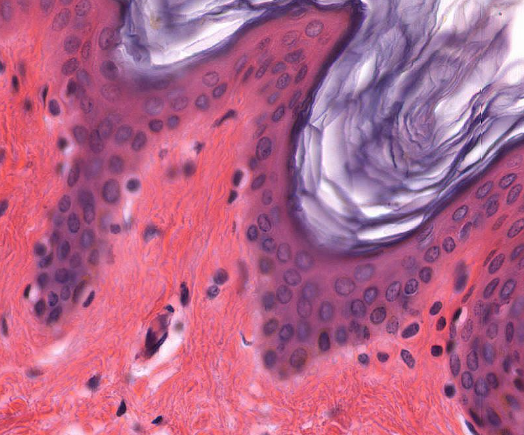

Keratinized Stratified Squamous Epithelial Tissue